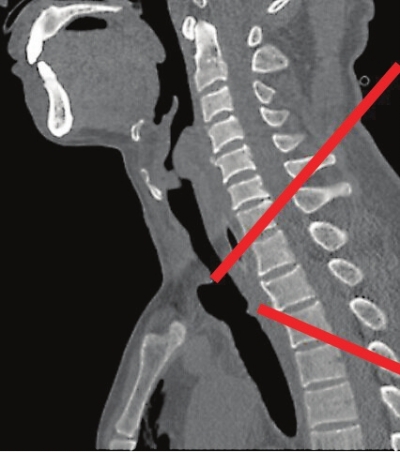

术前,两处红线可见王先生的气管断裂成两段

当晚10时左右,在经过简单的止血后,王先生被紧急送往医院神经外科手术室进一步手术。神经外科主任袁邦清从王先生的胸部CT片中看到,王先生位于颈部正中间的主气管,部分层面气管轮廓不清,前上胸壁皮下气肿合并纵膈气肿,整个气管完全斜断裂成两截,断裂下端被肺部重力牵拉,和断裂上端形成3cm的间距。